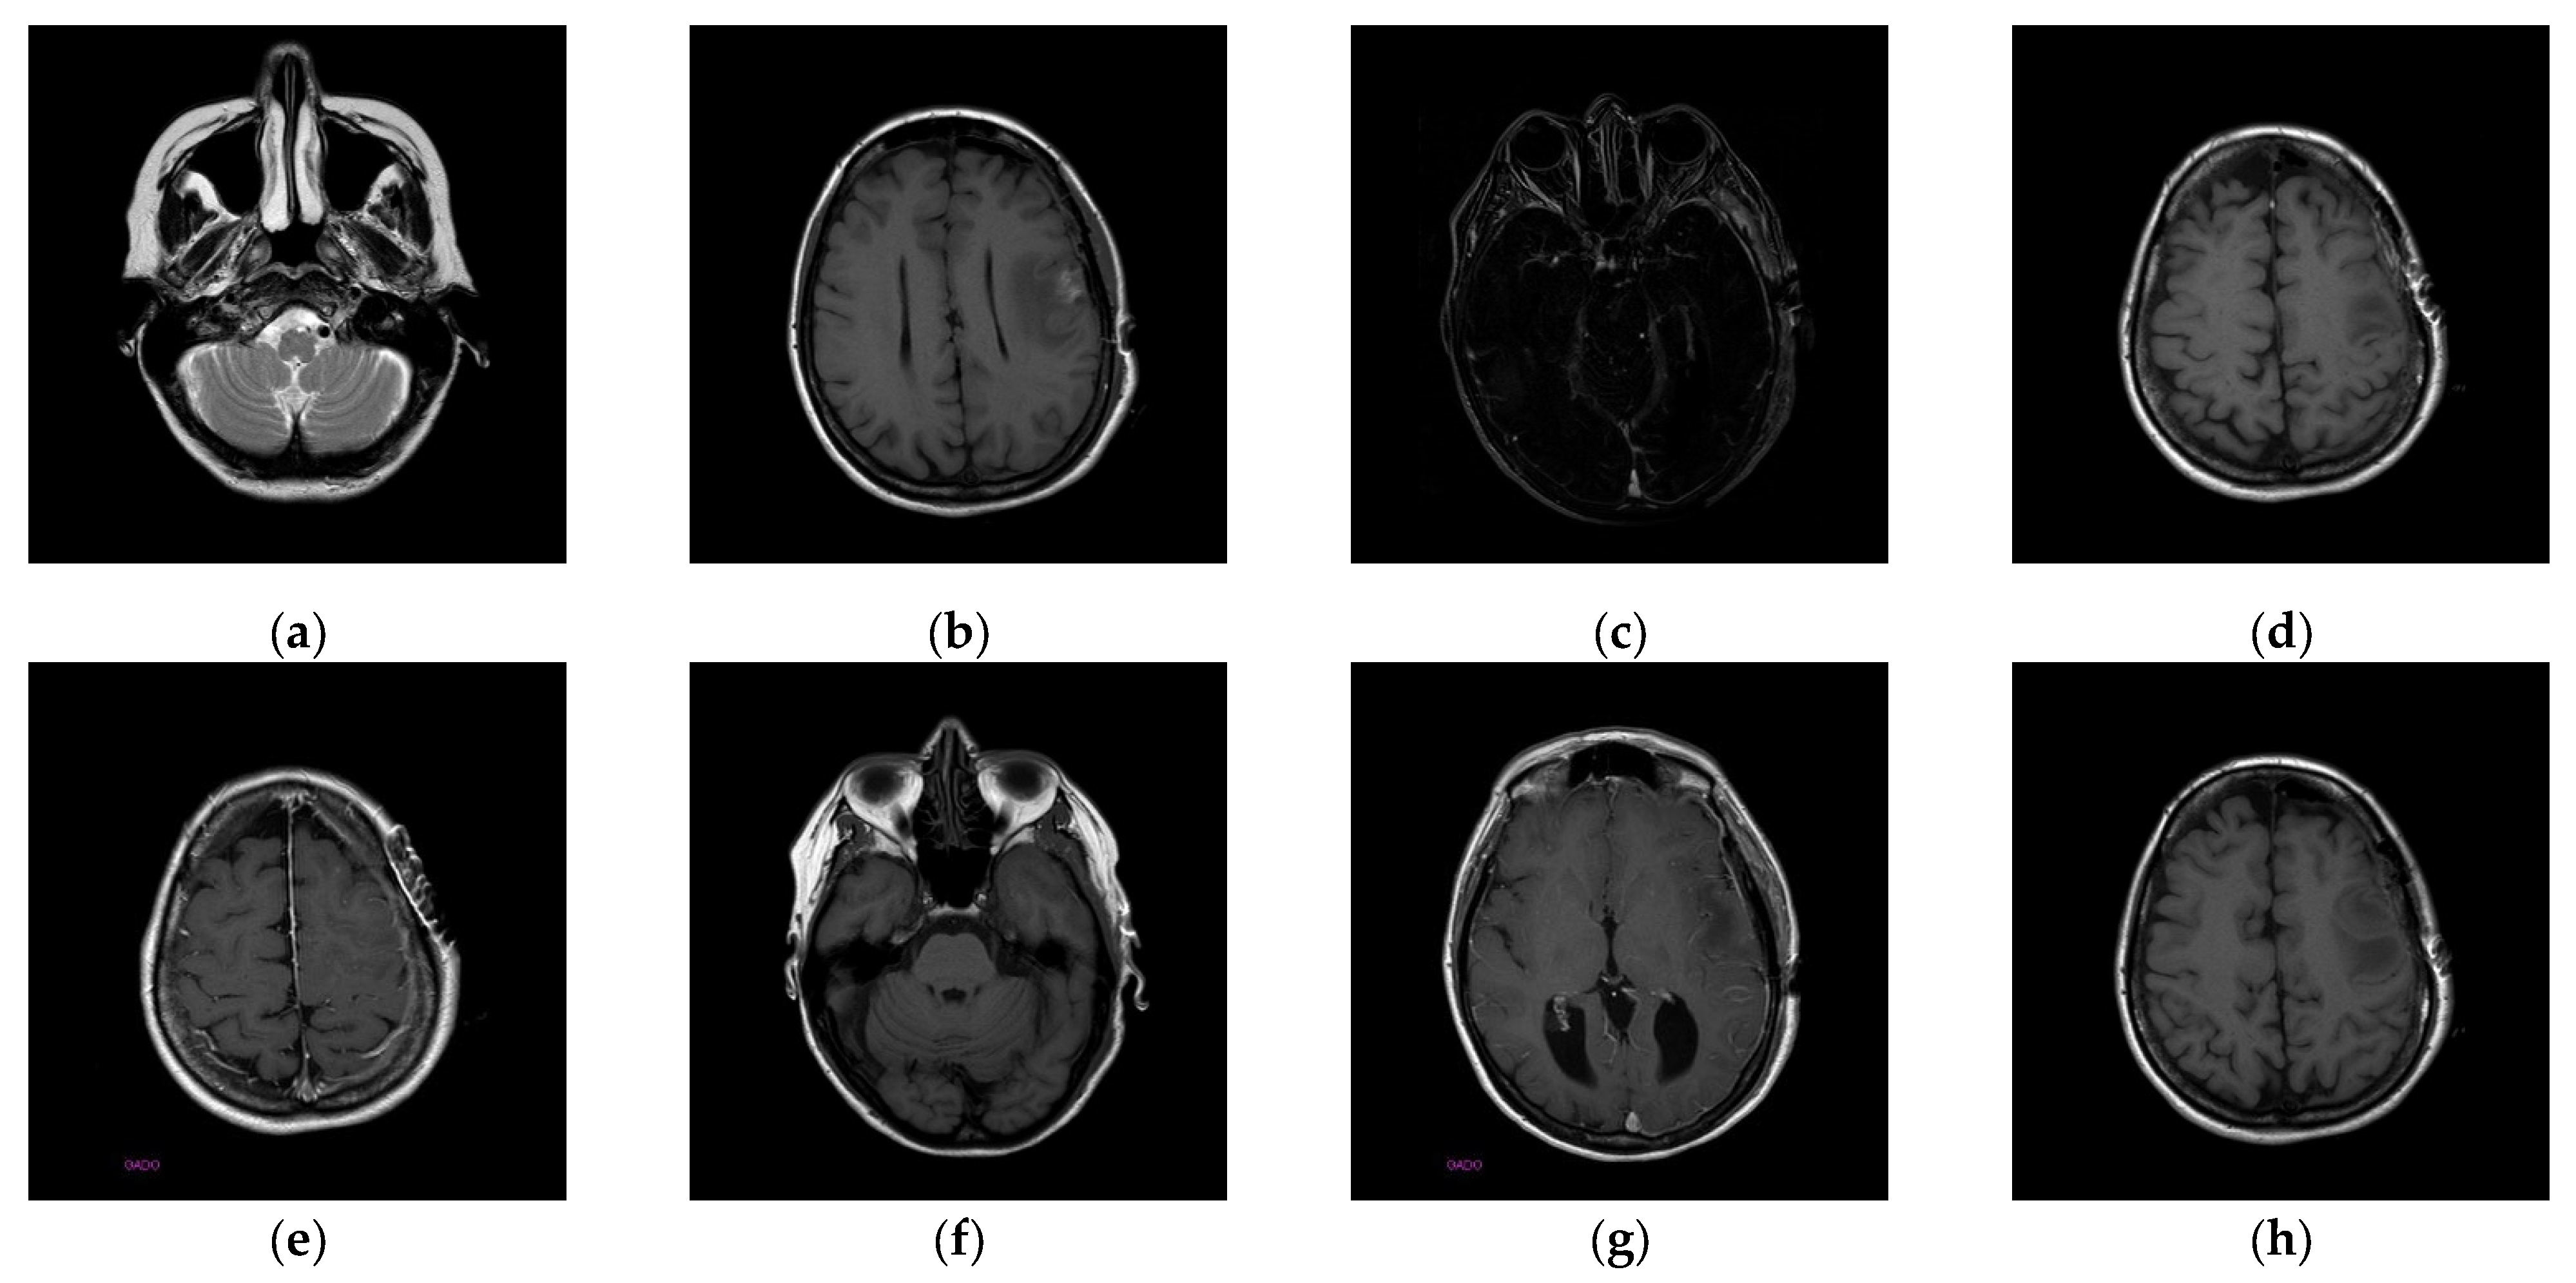

To better align our VUF-MIWS with the practical needs of clinicians for authenticating medical image sources, we conducted a pilot interview at a regional hospital. In this interview, we defined the critical diagnostic reference area of a medical image as the ROI (Region of Interest) and divided it into nine sub-regions, as shown in Figure 14. We then asked seven doctors to indicate their two most preferred locations for visible watermarks. Based on the collected feedback, sub-region A received the highest number of votes (a total of nine), followed by sub-regions E and I (both receiving five votes). Therefore, sub-region A was selected as the watermark position for the first and second experiments. The resulting watermarked images for the first experiments are displayed in Figure 15.

Figure 15. Eight watermarked images. (a) Watermarked 10.png; (b) Watermarked 11.png; (c) Watermarked 14.png; (d) Watermarked 16.png; (e) Watermarked 19.png; (f) Watermarked 26.png; (g) Watermarked 31.png; (h) Watermarked 57.png.